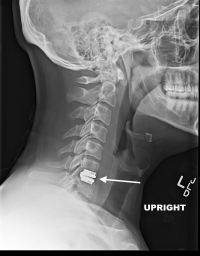

(Click to Enlarge Image) This is a Synthes artificial disc replacement at C6-7. The arrow points to the disc.